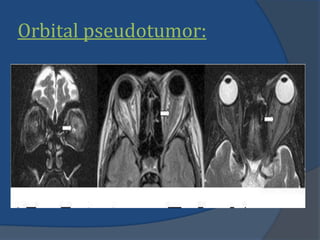

Orbital pseudotumor:

 MR imaging:

 Hypointense tonormal

muscle on TIWIs.

 Iso-intense to slighly

hyper-intense on

T2WIs and STIR.

 Due to high cellular

component and

fibrosis.

 Marked diffuse in-

homogenous

enhancement.

Orbital pseudotumor:  MRimaging:  Hypointense tonormal muscle on TIWIs.  Iso-intense to slighly hyper-intense on T2WIs and STIR.  Due to high cellular component and fibrosis.  Marked diffuse in- homogenous enhancement.